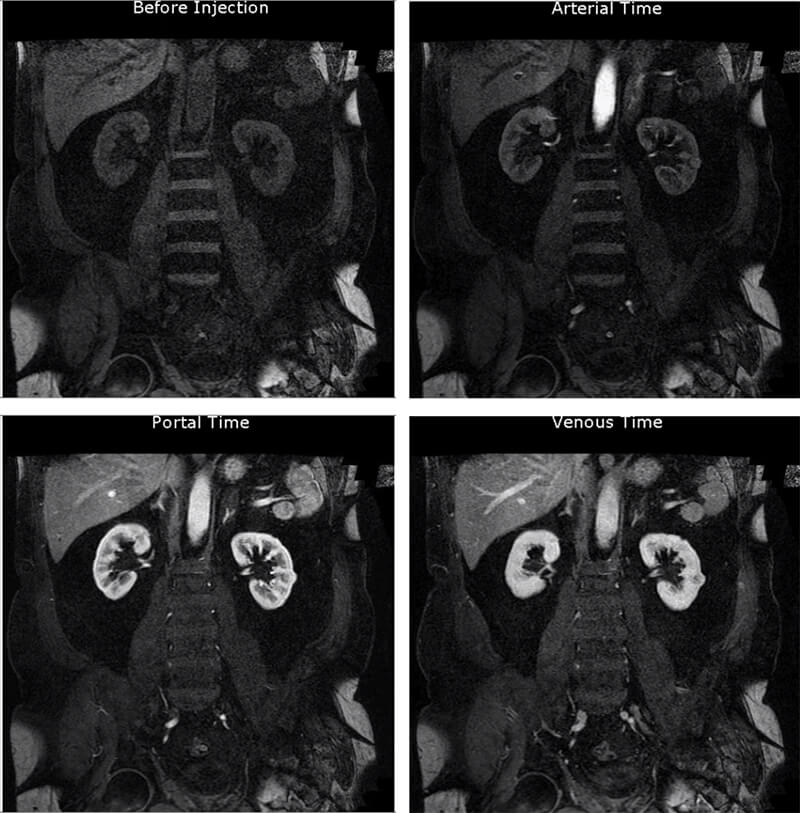

This image is a multiphase abdominal scan. An abdominal acquisition before injection, during the arterial phase, portal phase, and venous phase. We can also observe the vascular lesion of the left kidney.